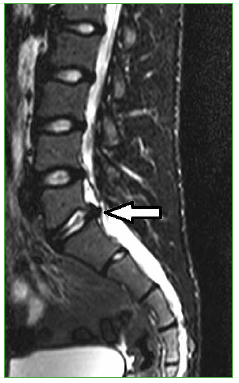

Figura 8.

Resonancia magnética, corte sagital ponderado en secuencia T2. La flecha señala la extrusión de L5-S1.